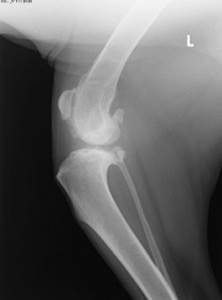

Диагностика разрыва крестовидной связки

Диагноз ставится врачом при осмотре – на основании клинической картины и рентгеновских снимков. Исключаются другие патологии с похожими симптомами – медиальный или латеральный вывих коленной чашечки, дисплазия ТБС. Все эти патологии могут накладываться друг на друга, запущенный медиальный вывих у мелких пород с возрастом может приводить к повреждению ПКС, но в любом случае необходимо их дифференцировать.

Также проверяется наличие симптома переднего “выдвижного ящика” – визуально наблюдаемое смещение большеберцовой кости краниально относительно бедренной.